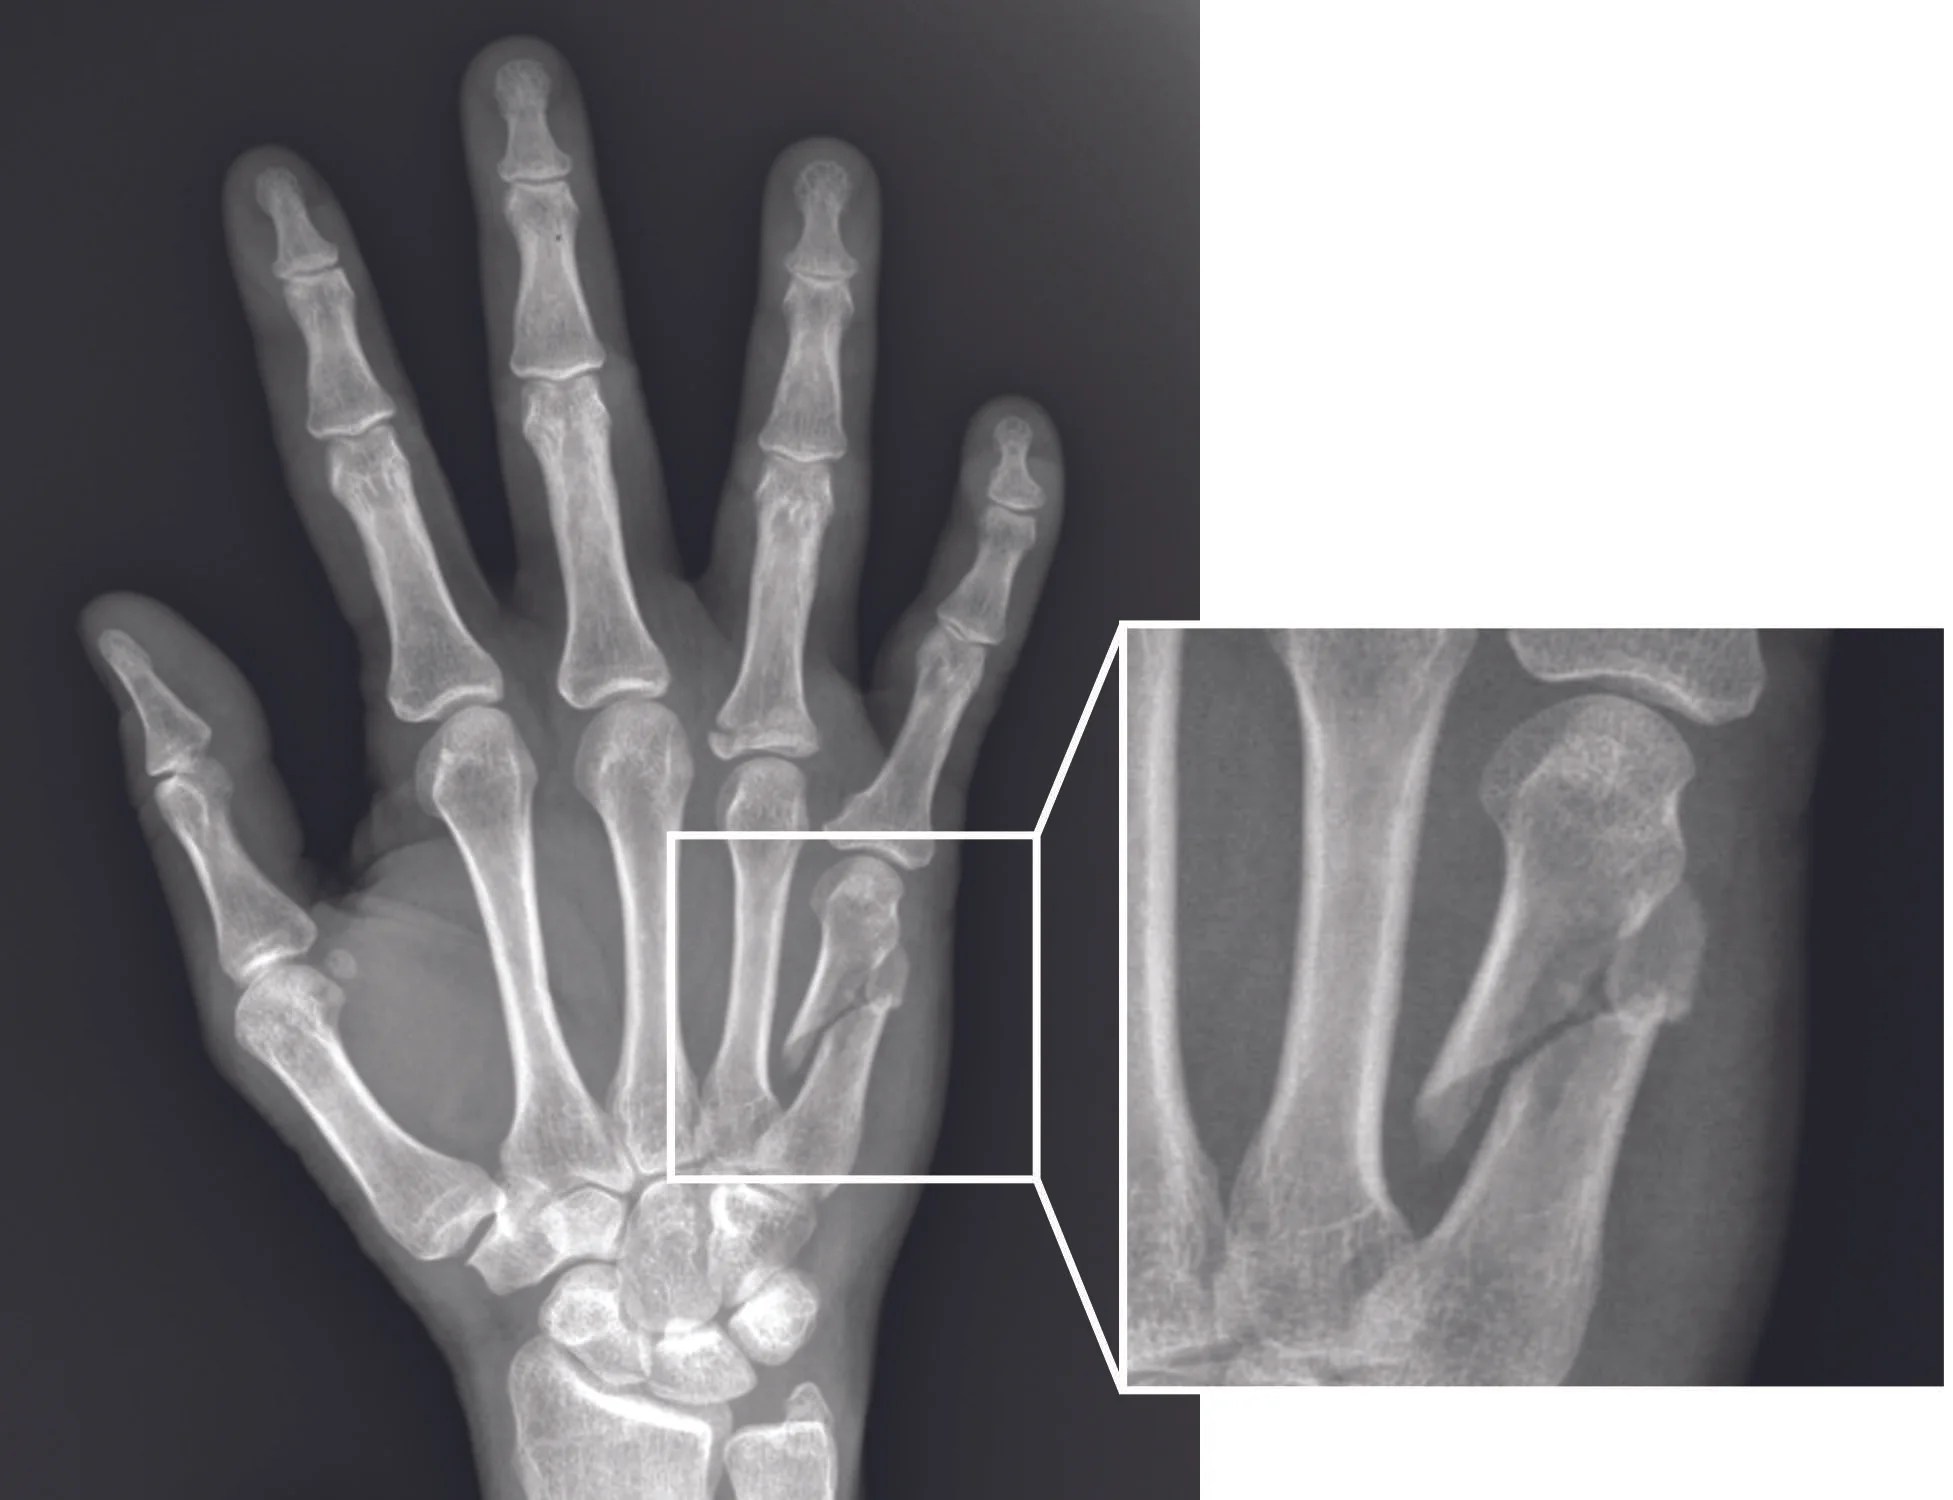

Un traumatólogo CDMX puede diferenciar entre una fractura, fisura, contusión, luxación, esguince o lesión muscular. Esta precisión es clave para elegir el tratamiento correcto, ya sea inmovilización, medicamentos, rehabilitación, seguimiento radiográfico o cirugía en casos específicos.

Las fracturas pueden presentarse en muñeca, tobillo, clavícula, cadera, rodilla, mano, pie, brazo o columna. Cada una necesita un manejo específico según el tipo de trazo, ubicación, edad del paciente y nivel de actividad.

Un traumatólogo CDMX puede indicar tratamiento conservador cuando la fractura es estable, o valorar cirugía cuando se requiere alinear y fijar el hueso. La recuperación adecuada no termina cuando baja el dolor, también implica recuperar fuerza, movilidad y confianza para volver a las actividades diarias.